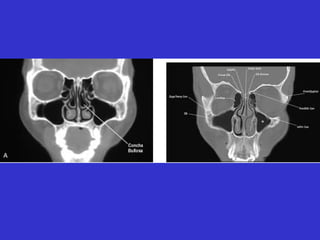

Este documento describe las diferentes proyecciones radiográficas utilizadas para examinar los senos paranasales, incluyendo las proyecciones básicas de Caldwell, Waters lateral y las proyecciones especiales como Hirtz y Waters mentonasal. También describe las diferentes estructuras anatómicas que componen el complejo ostiomeatal anterior y posterior de los senos paranasales.